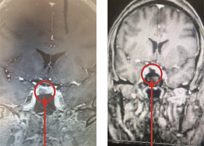

- Pituitary Tumors